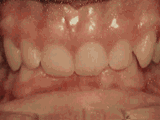

何小姐是幼儿园的老师,面部轮廊精致,却有一口歪牙,一度不敢露牙微笑,都说笑容是最好的名片,所以幼儿园的小宝宝们都对她避而远之。听说牙齿矫正能改变畸形牙,何小姐二话不说就在小诊所做了金属矫正,五个月过去后,牙齿畸形没有改善,侧脸却越发外凸。

意识到矫正失败,何小姐怒从心起,再次选择口腔机构慎之又慎!通过资质对比、亲自考察、查询认证等多途径,决定在时代天使隐形矫治示范基地麦芽口腔进行修复治疗。麦芽口腔正畸中心主任一语道破何小姐矫牙失败的原因,何小姐早期矫牙的医生判断失误,矫牙过程牵拉过早、频繁加力、力度过大,所以造成牙齿矫正力度外溢、致使外突。

时代天使隐形矫治示范基地麦芽口腔的正畸科主任经过系统的口腔全景片/头颅侧位片和口腔CT判定,现在严格把控矫正力度、制定分阶段矫牙方案,还能调整面型,将其挽救回来。正畸修复治疗后,何小姐露出了久违的笑容,牙齿不齐终于得到解决,面型也得到了纠正。